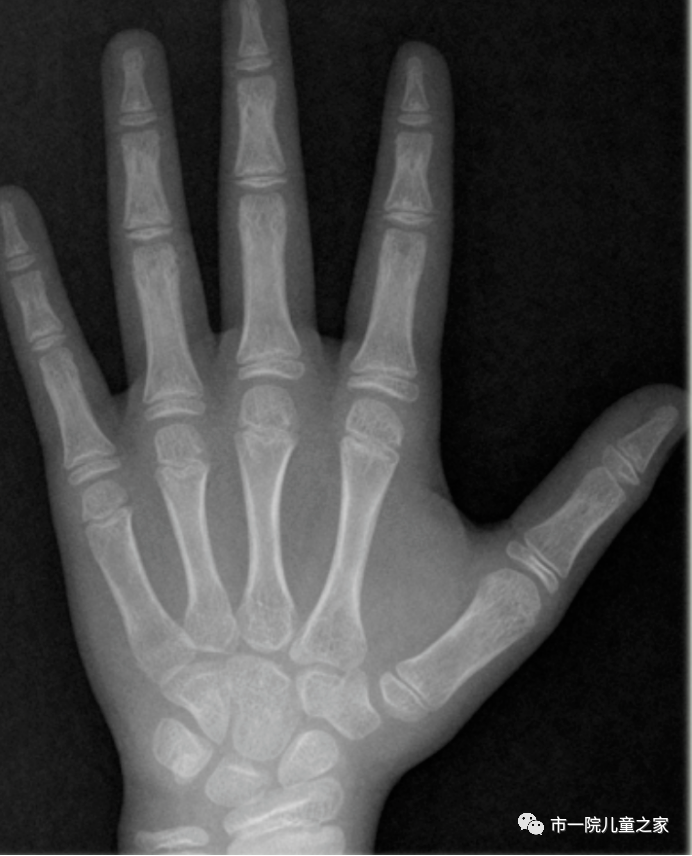

关注孩子身高,家长要学会定期对孩子的身高进行监测,不仅与同龄孩子比较,还要与孩子自己前一年的身高比较,以了解孩子的生长速度。在医院拍摄骨龄片,医生就可通过身高、骨龄、生长发育状况来综合评估。

骨龄与身材矮小的关系

骨龄是衡量儿童生长发育的最重要指标,若是骨龄偏大的身材矮小儿童,其骨骼生长的潜力低,一旦骨骺闭合就基本再无长高的机会,反之骨龄偏小则代表孩子骨骼生长潜力仍有一定的空间。所以说,骨龄可以为身材矮小儿童的骨骼发育评估和生长潜力预测提供科学的参考依据。如果孩子骨龄落后实际年龄1岁以上且生长速率基本每年均可达到正常水平,则可能为晚长或体质性青春期发育延迟。